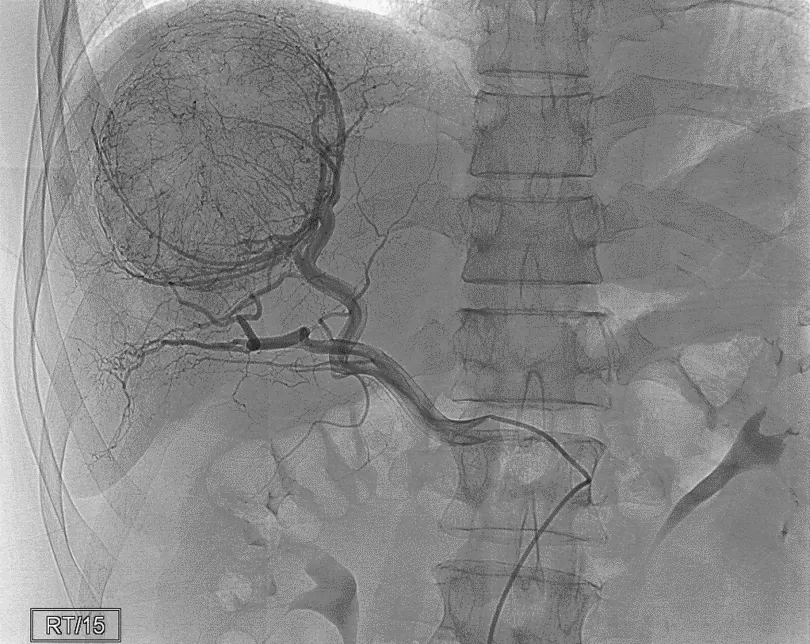

Hình 1: Chụp mạch máu gan để xác định nguồn cấp máu cho khối u gan phải,

giúp xác định nhánh mạch nuôi khối u để điều trị nút mạch hoá chất ung thư biểu mô tế bào gan (HCC)